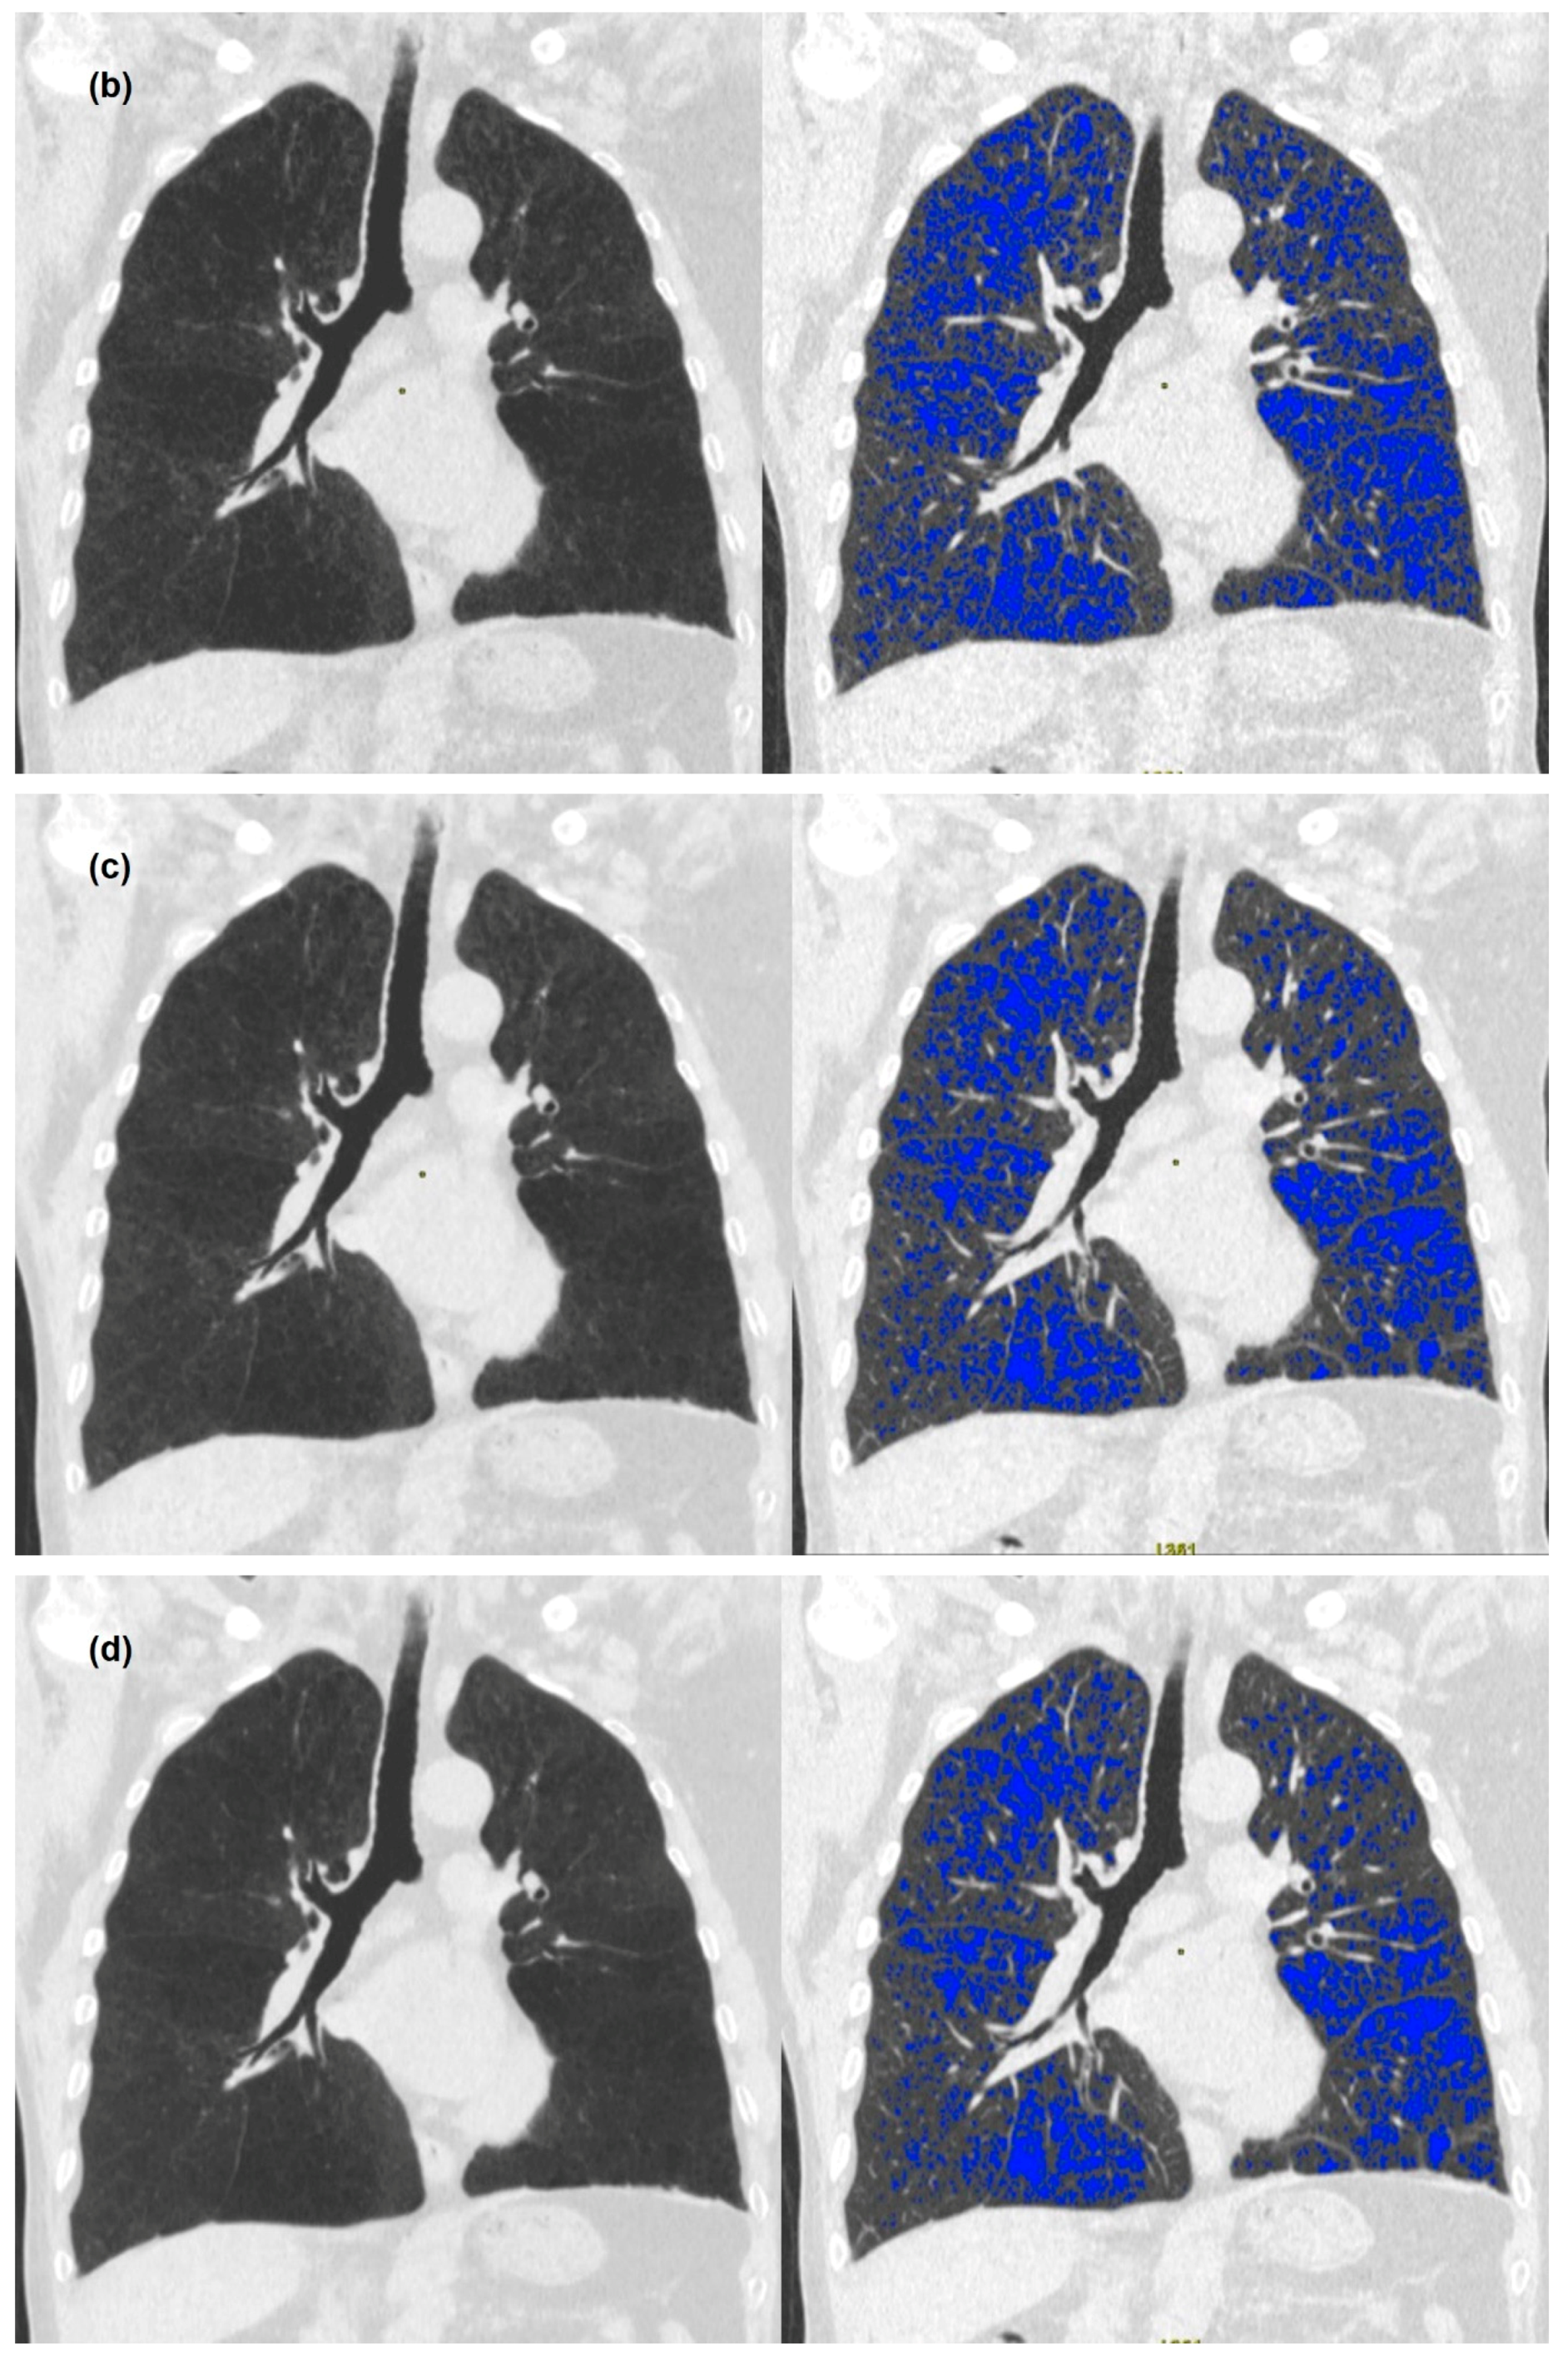

2.3. Image Analysis

3.2. Quantitative Measurements of Standard-Dose and Ultra-Low-Dose CT